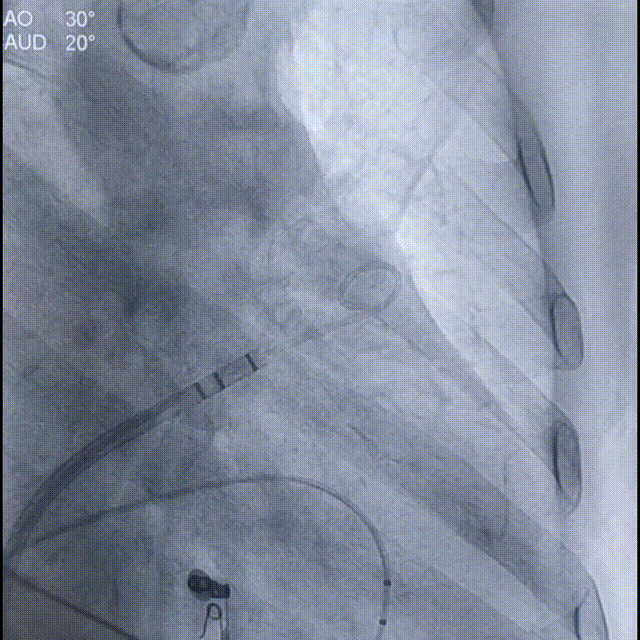

通过LAA造影和工作体位测量,结果显示患者左心耳开口直径为25mm,着陆区直径为20mm,深度为32mm;根据数据,手术团队决定选择Laager®封堵器2429型号进行后续操作;

工作体位造影